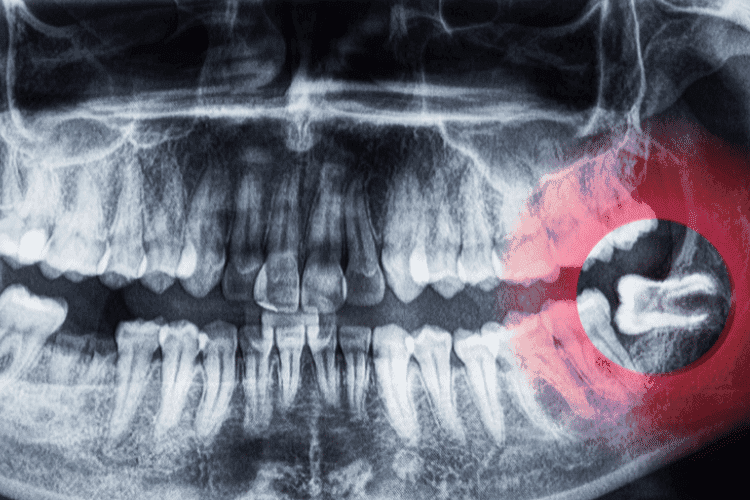

Dental X-ray highlighting wisdom teeth impaction.

Smaller jaws often mean there isn’t enough room for the four wisdom teeth to erupt normally. This can lead to impacted teeth, which is when the tooth hits your jawbone or the tooth next to it and gets stuck. When this happens, you will experience a lot of pressure and a deep throbbing ache in your bone. Your teeth may move to accommodate the molar, resulting in a feeling of tightness around the teeth.